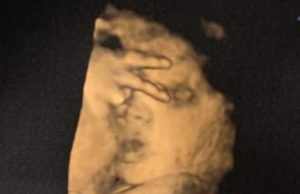

Un bebeluș nenăscut i-a spus mamei sale „du-te dracu” în timpul...

O femeie însărcinată a avut un șoc hilar atunci când în timpul unei scanări cu ultrasunete și-a auzit bebelușul nenăscut spunându-i „du-te dracu”. Se pare...